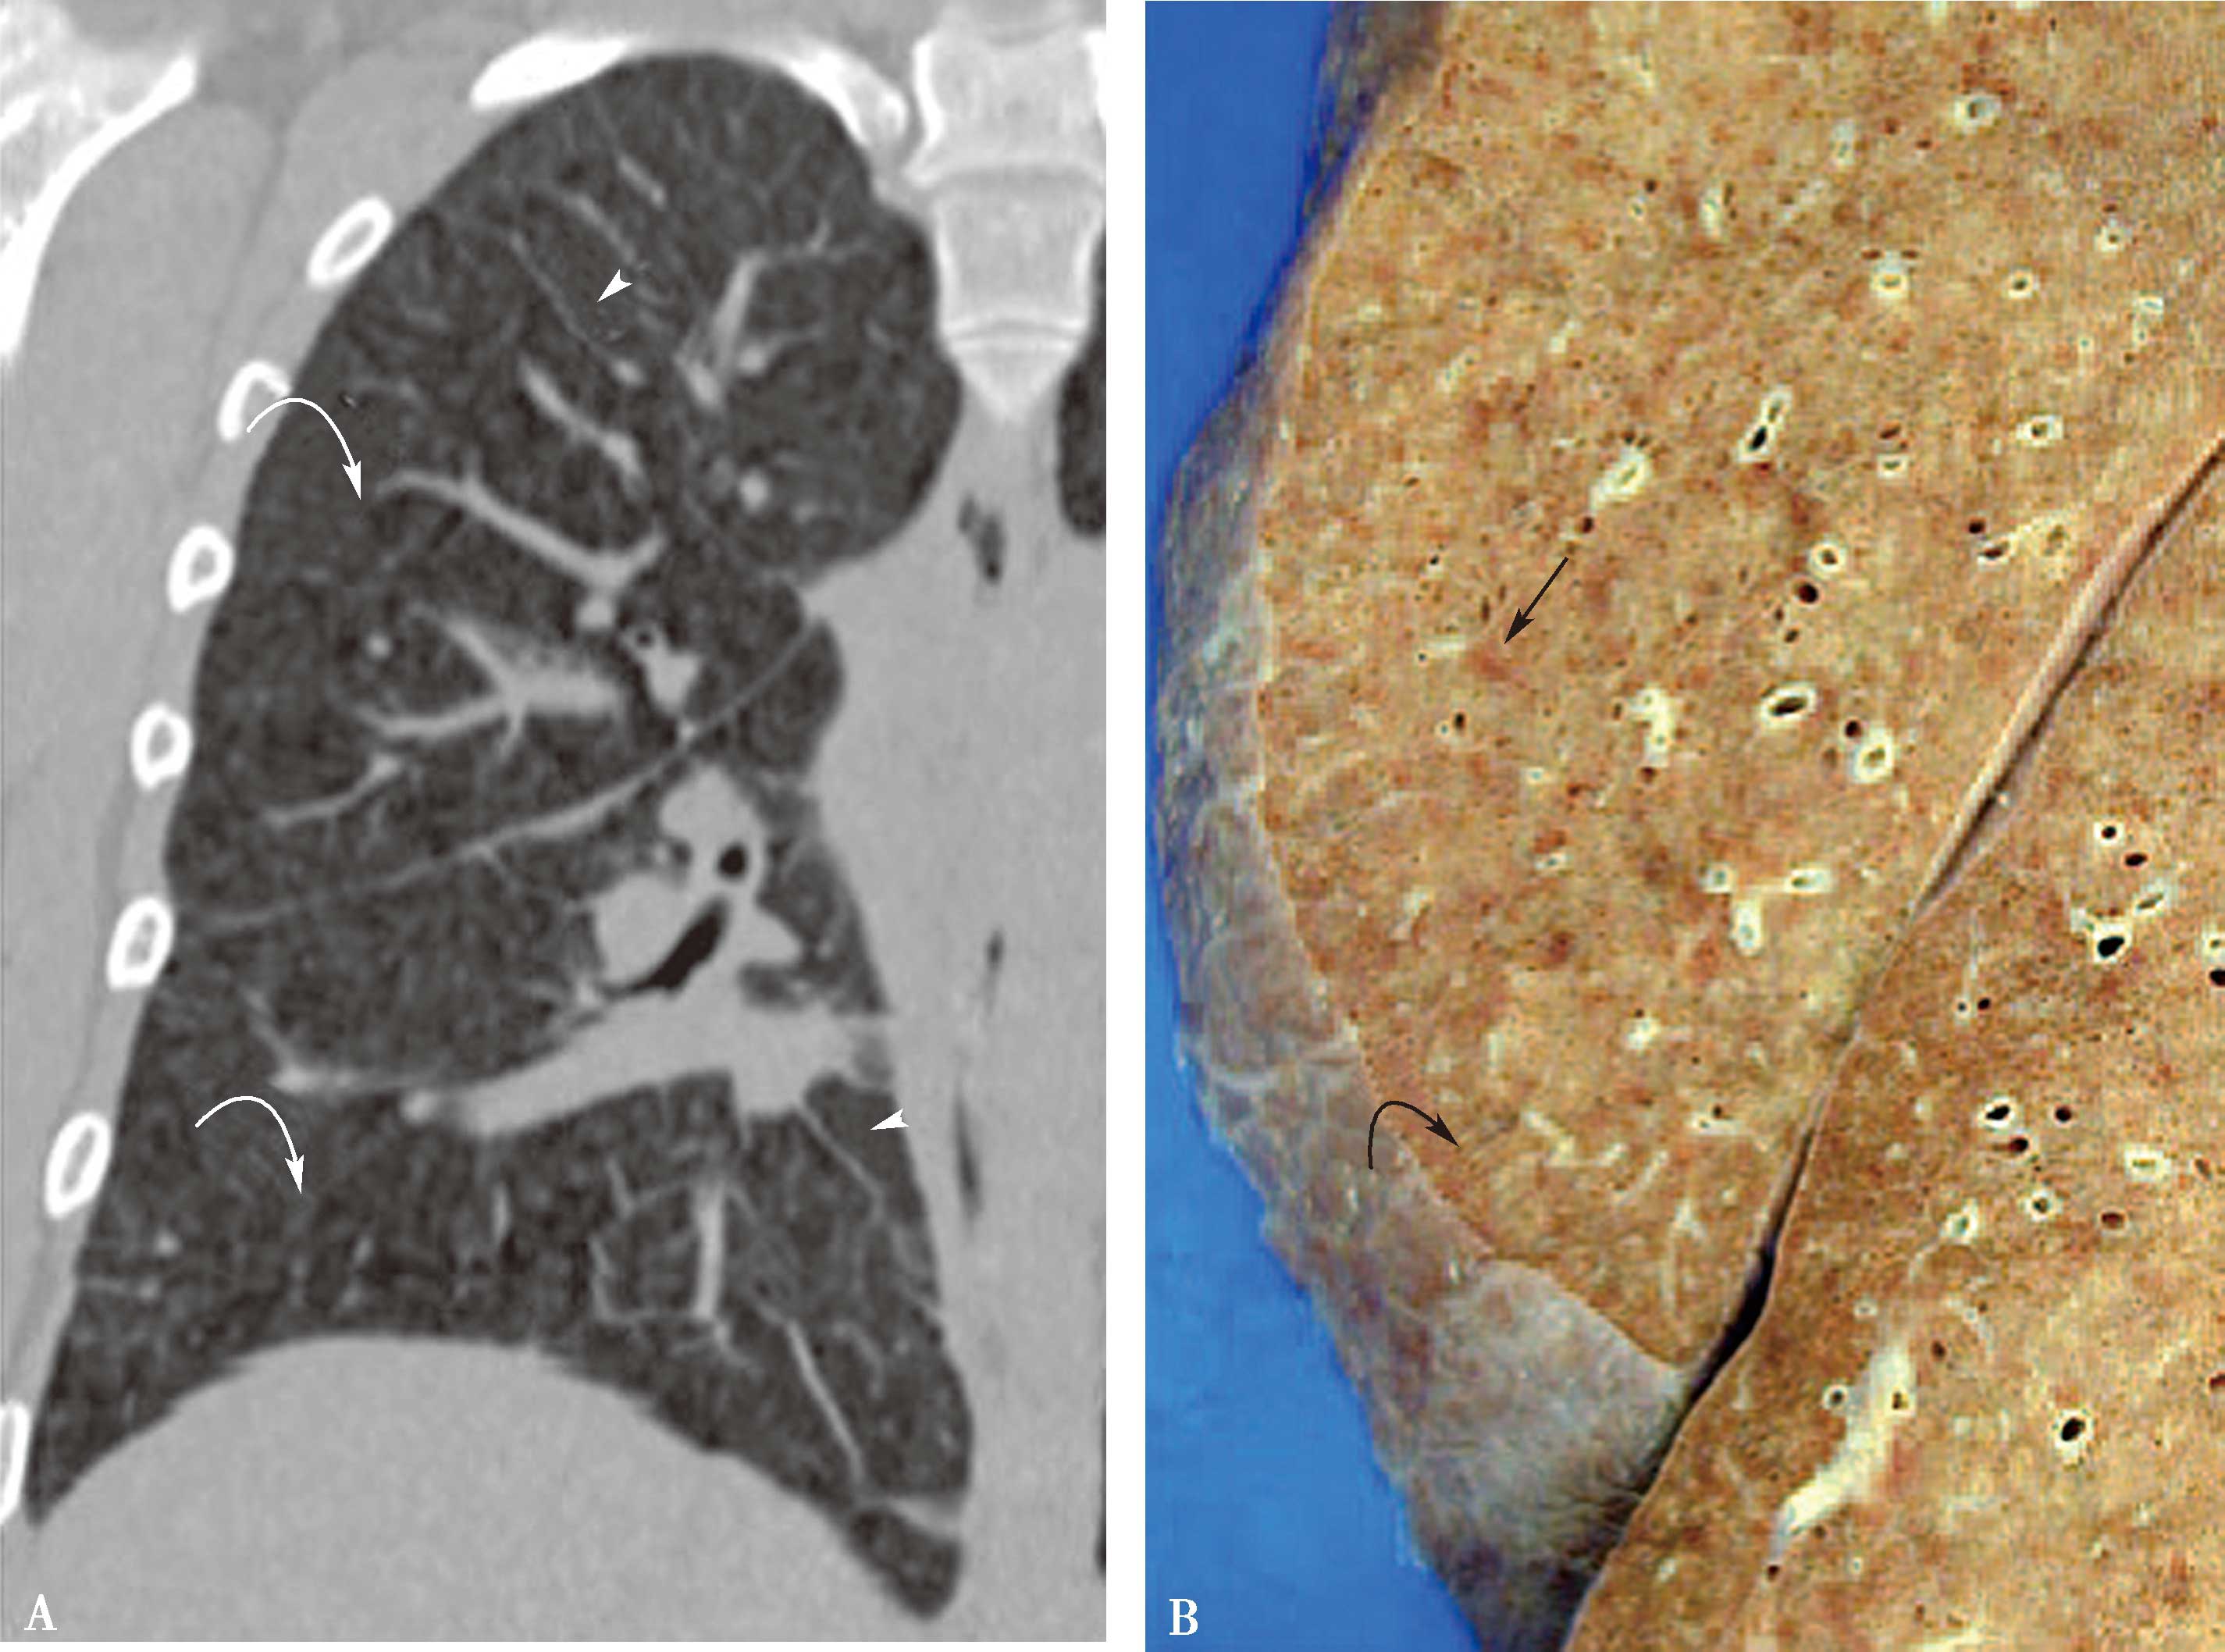

图8-10-3 PVOD女,17岁,喘憋,病理诊断:肺静脉阻塞病

A.CT冠状位重建(肺窗)显示广泛小叶间隔线和弥漫的边缘不清的磨玻璃结节影(箭头);B.右肺组织标本大体照显示间隔线增厚(曲箭头),边缘不清的淡红棕色实质结节灶(直箭头);C.横断图像(纵隔窗)显示右心房、右心室明显增大,右心室前壁增厚(弯箭头),室间隔平直(↑);D.右心房、右心室病理镜下所见小静脉阻塞(↑)